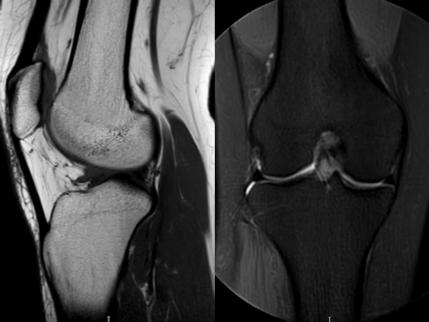

5. 夜間持續(xù)性鈍痛——骨骼的“暗夜低語”

場(chǎng)景:無外傷卻夜間痛醒,膝蓋仿佛“壓著巨石”

MRI偵查:篩查骨腫瘤、骨髓水腫(X線看不見的“內(nèi)傷”),警惕“沉默殺手”

(骨髓水腫)